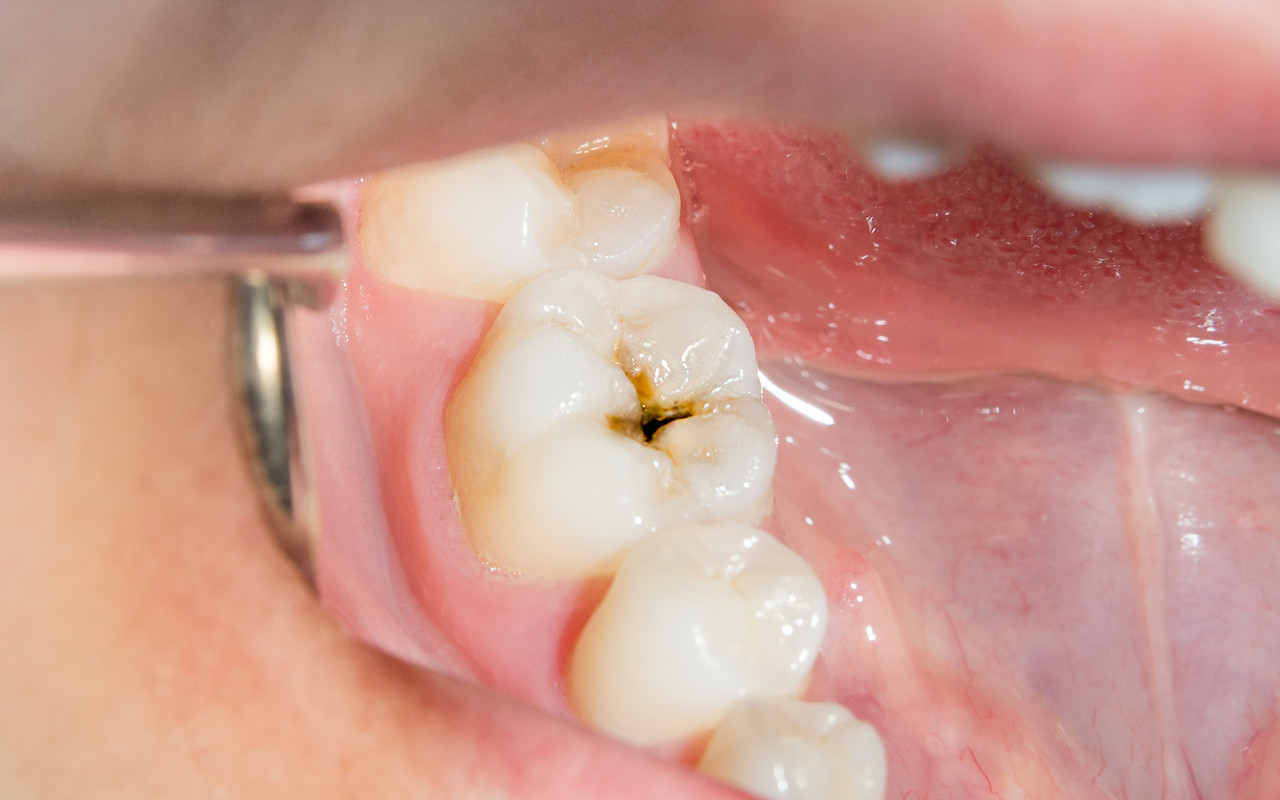

· 치아에 검은 점이나 구멍이 보이기도 한다.

충치 단계별 치료방법

그 통증은 세균이 치아를 파고드는 신호일 수 있습니다.

충치의 깊이를 정확히 진단하는 것이 먼저입니다.

충치는 진행 단계에 따라 증상과 치료법이 완전히 달라집니다.

닥터조 치과는 현재 상태에 맞는 가장 좋은 방법을 정직하게 제시합니다.